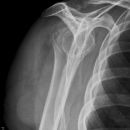

Dislozierte subcapitale Fraktur mit Tbc majus

Subcapitale Fraktur und Tuberculum majus